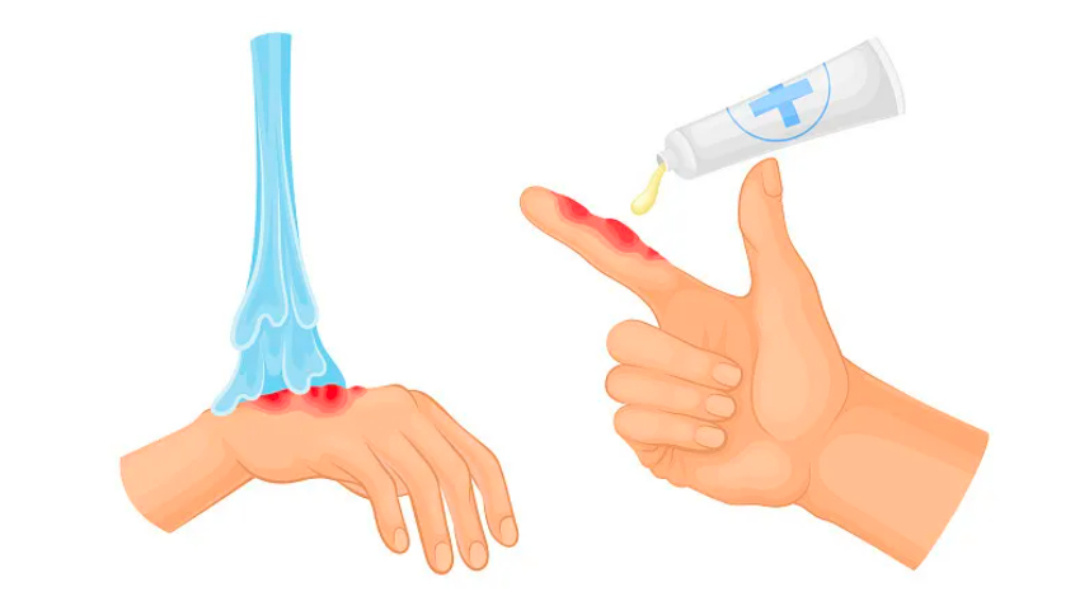

六、烫伤起水泡切勿自行戳破,专业处理才能避免感染留疤

手脚被高温烫伤后起水泡,是生活中很常见的意外伤害,很多人会下意识用针、指甲把水泡戳破,觉得放出水就能好得更快,这种做法大错特错。烫伤后的水泡,外层的泡皮是一层天然的保护屏障,能隔绝外界细菌、病毒,避免伤口感染,同时减少伤口与外界摩擦产生的疼痛感。

自行用未经消毒的针、剪刀戳破水泡,一方面会产生剧烈疼痛,另一方面极易引发外界细菌侵入伤口,导致伤口红肿、化脓、感染,加深烫伤创面,不仅延长愈合时间,还会留下永久性的色素沉着和疤痕。如果水泡体积较小,没有影响正常走路、穿鞋,无需任何处理,保持伤口干燥清洁,水泡会自行吸收、干瘪、愈合,如果水泡体积较大,严重影响日常活动,一定要前往医院,由医生用无菌器械进行消毒、引流、包扎,全程无菌操作,最大程度保护伤口,降低感染和留疤风险。

另外,烫伤后第一时间的急救也很关键,立刻用流动的冷水冲洗伤口15-30分钟,降低皮肤表面温度,减轻深层组织损伤,切勿涂抹牙膏、酱油、香油等偏方,否则会加重伤口感染,影响医生判断伤情。